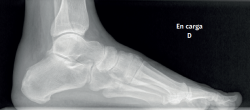

The dorsoplantar and sagittal views of both feet under loading conditions are indicated, together with the posteroanterior view of the ankles under loading conditions.

Figure 3. Plain radiography, Sagittal view with weight-bearing. Moderate calcifications in the insertion of the Achilles tendon with intratendinous enthesophyte. Morphological alterations of the posterior tuberosity of the calcaneus.

Plain radiography under loading conditions is the essential initial diagnostic tool(20). It allows us to assess alignments and dysmetria, to measure angles, to determine the morphology of the calcaneus and its posterior tuberosity, to characterise bone exostosis and increments in thickness of the retrocalcaneal soft tissues, and to plan surgical procedures (Figure 3).